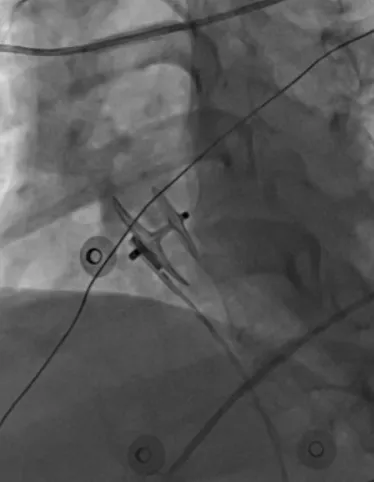

該患者有多年的頭痛病史,經(jīng)神經(jīng)內(nèi)科篩查考慮為PFO,并經(jīng)過規(guī)范藥物治療,效果不明顯,來PFO專病門診找到醫(yī)院心血管內(nèi)五科副主任牛和平,經(jīng)過仔細(xì)詢問病史,查看相關(guān)檢查結(jié)果,診斷PFO明確,考慮患者有介入封堵的指征,而后收入院。但患者患有先天脊柱側(cè)彎及后突,血管及心臟結(jié)構(gòu)有明顯轉(zhuǎn)位,常規(guī)超聲并不能完全準(zhǔn)確引導(dǎo)介入操作,為介入手術(shù)帶來極大的困難和風(fēng)險。醫(yī)院副院長、心血管內(nèi)五科主任張軍教授,副主任牛和平,副主任付金國,副主任醫(yī)師王磊,主治醫(yī)師于愷等反復(fù)討論,決定實施ICE指導(dǎo)下PFO介入封堵術(shù)。術(shù)中,在ICE的實時引導(dǎo)下,傳送鞘管順利進(jìn)入右心房,明確PFO的位置后導(dǎo)絲成功通過未閉卵圓孔進(jìn)入左房,之后順利植入封堵器,ICE實時確認(rèn)封堵術(shù)釋放位置良好,封堵效果極佳,手術(shù)時間不到半小時,患者恢復(fù)良好,目前已經(jīng)出院。

與常規(guī)經(jīng)胸超聲相比,ICE 具有更高的圖像分辨率,依靠其探頭的靈活性,可從多個切面對房間隔成像,有助于精確測量卵圓窩的直徑、房間隔的長度、PFO隧道長或?qū)挕?隧道入口及出口直徑;同時可以觀察 PFO 患者心 房水平的分流情況,明確有無過長的 Eustachian 瓣 或Chiari網(wǎng)、ASA、雙層隔等特殊的復(fù)雜結(jié)構(gòu)。介入封堵術(shù)中,ICE 能實時監(jiān)測并指導(dǎo)手術(shù)過程,幫助術(shù)者精準(zhǔn)確定 PFO 的位置,全程直視下釋放封堵器,評 價封堵器的形狀、位置和穩(wěn)定性。同時,可通過注 射生理鹽水和(或)彩色多普勒檢查來確認(rèn)有無殘 余分流。在 TTE 聲窗差、不耐受 TEE、解剖特征復(fù) 雜型 PFO、PFO 封堵術(shù)后殘余漏二次介入的患者 中,ICE引導(dǎo)或輔助下進(jìn)行 PFO封堵術(shù)能明顯提高手術(shù)成功率。ICE的另一優(yōu)勢是可減少術(shù)中X線暴 露時間,有效降低對患者(特別是肥胖者)和術(shù)者的 輻射危害。